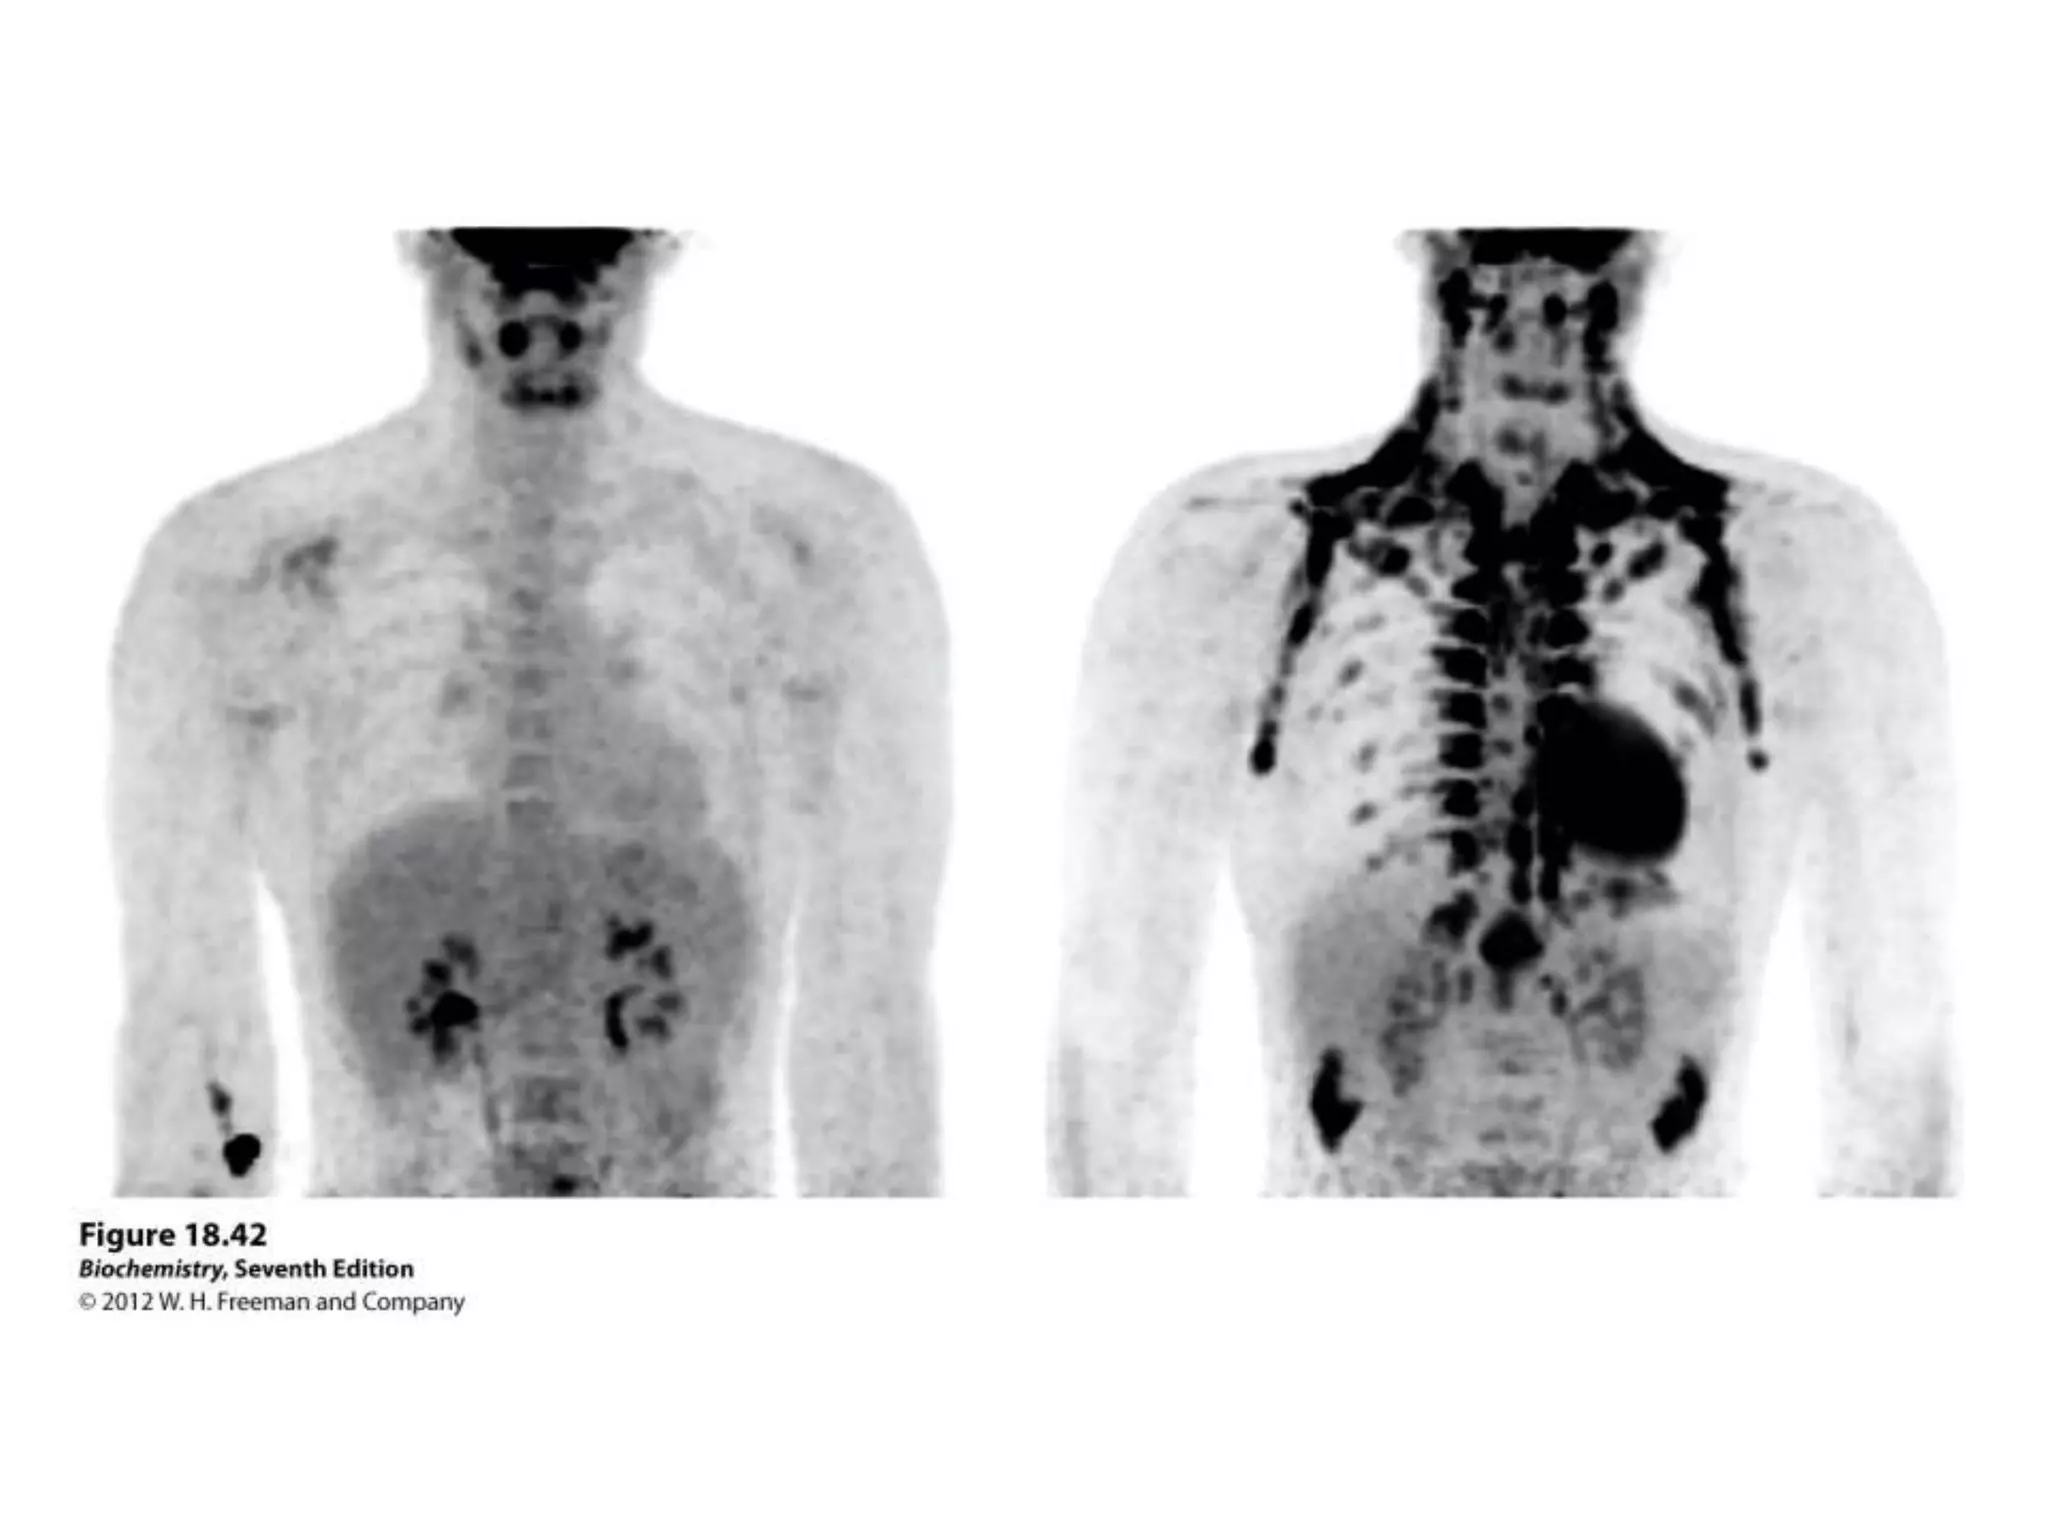

Tumor Cells

   Regulation is gone in catabolic

processes

   Glycolysis is faster than TCA

   They use more Glc, but cannot

oxidize pyruvate

   Pyruvate  lactate

(PH decreases in tm.)